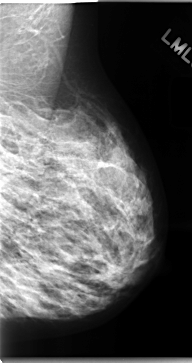

C_0098_1.LEFT_MLO

LEFT_MLO LINES 4712 PIXELS_PER_LINE 2496 BITS_PER_PIXEL 12 RESOLUTION 50 NON_OVERLAY